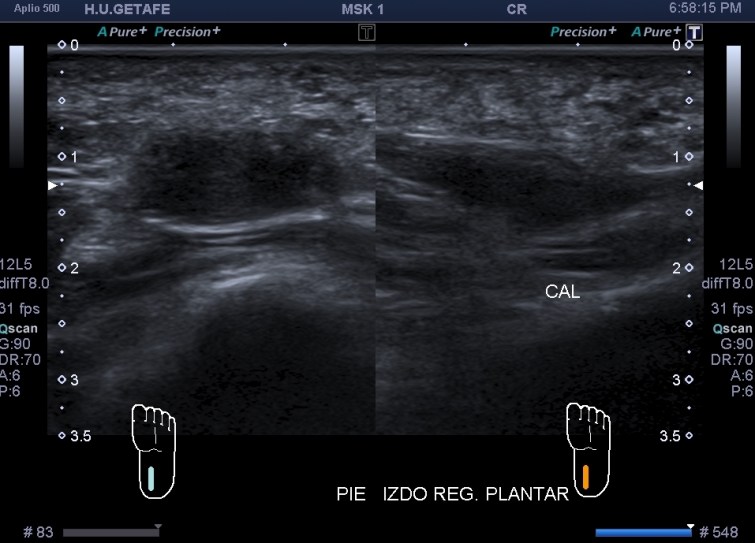

En este caso final una mujer acude a realizarse una ecografía con una petición de su médico de cabecera, viene por aumento del calibre del muslo anterior, no refiere dolor, no cuenta traumatismo previo.

La exploración es la habitual, revisión sistemática de toda la ecoarquitectura musculoesquelética de la cara anterior del muslo, dirigido al Cuádriceps.

Me llama poderosamente la atención, lo recuerdo perfectamente, la normalidad del recto anterior, pero después de buscar un poco observo como el vasto intermedio si está «distinto», algo heterogéneo, voy a comparar con el lado contralateral y bingo¡ el vasto intermedio, que es de esa musculatura «que nunca tiene nada», modo «ironía on», te sorprende…y la ecografía muscular es como el océano, nunca puedes confiarte…

Mira las imágenes y tu misma te darás cuenta:

La zona que presenta mayor abombamiento y empastamiento (cara lateral del muslo izquierdo), se visualiza aumento del grosor del fascículo muscular correspondiente con el vasto intermedio, sin poder evidenciarse la presencia de lesiones definidas. El diagnóstico es un aumento difuso e inespecífico del Vasto Intermedio, sin masas ni roturas. A valorar con RMN.